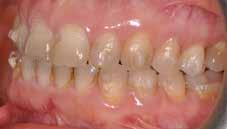

A felnőtt páciensek kezelése során általában egyszerre több ellátásra szoruló elváltozást is diagnosztizálhatunk: hiányzó fogak, kopott fogazat, esetleg régi, nem megfelelő, sérült fogpótlások, rendellenes helyzetben lévő fogak stb… Ezen páciensek kezelésekkel kapcsolatos kérései mindig az esztétikai vagy a rágással kapcsolatos kívánságaik kielégítését szolgálja. A kezelések során a fogorvosoknak nem csak a páciensek kéréseinek teljesítésére, hanem ezzel egyidejűleg a fogazat általános megjelenésének és funkciójának lehetőség szerinti javítására is törekedniük kell. Mindemellett a lehető legtöbb saját foganyag megőrzését és az évek során elvesztett kemény- és lágyrészek pótlását (pl.: hiányzó fogak, sorvadt állcsontgerinc, lágyszöveti defektusok) is szem előtt kell tartaniuk, úgy, hogy közben egy hosszú távon fenntartható eredményekkel járó kezelési tervet állítanak össze. Ezek mindig összetett esetek. Annak érdekében, hogy a fentiekben megfogalmazott összes kezelési célt teljesíteni tudjuk, interdiszciplináris megközelítésre van szükség. Az ilyen komplex rehabilitációs kezeléseket „fogászati megfiatalításnak” nevezzük. Ezeknek a beavatkozásoknak lényege az elhasználódott fogazat biológiai szempontokat figyelembe vevő minimál invazív módon történő helyreállításában rejlik, mely folyamat végére a páciensek fogai visszanyerhetik fiatalkori megjelenésüket.

A rehabilitációs kezeléseknek a célja, hogy a páciensek a lehető leghosszabb időn keresztül képesek legyenek mosolyogni és rágni. A protetikai kezeléseket végző fogorvosoknak helyre kell tudni állítaniuk a fogívek szabályos lefutását és az alsó és felső fogív között megfelelő interokkluzális érintkezéseket kell létrehozniuk. Így lehet csak az ellátás befejezését követően elért végeredmény biológiai szempontokat figyelembe vevő esztétikáját, funkcionális megfelelőségét, hosszú távú fenntarthatóságát biztosítani.

Nagyon fontos, hogy már a kezelések elején meghatározzuk, hogy melyek azok a hiányzó fogak, amelyeket a későbbiekben pótolni szeretnénk, valamint helyesen diagnosztizáljuk a kariológiai, endodonciai vagy parodontológiai okok miatt ellátást igénylő elváltozásokat. Szintén kiemelt jelentőséggel bír a fogak megtarthatóságának kiértékelése. A kezelési terv felállítása során tisztában kell lennünk azzal, hogy mely fogak alkalmasak fogpótlások ideiglenes vagy végleges elhorgonyzására.

A fogszabályzó kezelések egyik legfontosabb célja, hogy elérjük a lehető legharmonikusabb interokkluzális fogérintkezéseket, továbbá az állcsont relációs helyzetének frontális és szaggitális síkban is megfelelőnek kell lennie. A fogszabályzás befejezésekor a fogpozícióknak nem orthodonciai, hanem protetikai szempontok szerint kell ideálisnak lenniük. Az Invisalign ClinCheck szoftver (Align Technology) segítségével a protetikus az orthodontussal együtt meg tudja határozni azokat a végső fogpozíciókat, amelyek a lehető legjobb végeredmény biztosításához elengedhetetlenek. Bizonyos klinikai paramétereket, mint a fogak klinikai koronájának nagyságát, az egyes fogak fogíven belüli optimális pozícióját, a fogívek egymáshoz viszonyított helyzetét, a fogak között látható rések nagyságát, a frontfogak tengelyének dőlését, az overjet és overbite mértékét már a kezelések megkezdése előtt pontosan definiálni kell. Ezeket az adatokat viszont csak a tervezett végleges fogpótlás ismeretében lehet meghatározni, ezért van szükség az orthodontus és a protetikus szoros együttműködésére.